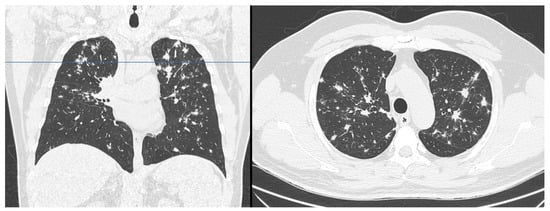

2. Case Presentation